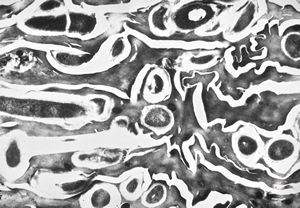

M,54y. | Whipple disease - duodenum

F,41y. | Whipple disease - duodenum

Whipple disease - duodenum